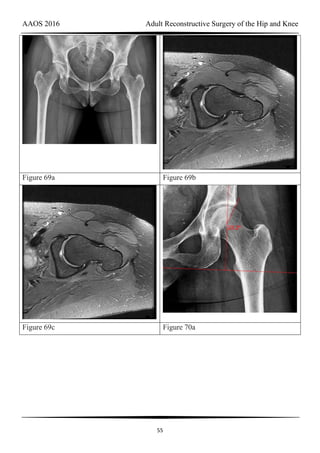

Figure 69a Figure 69b

Figure 69c Figure 70a

CLINICAL SITUATION FOR QUESTIONS 69 THROUGH 72

Figures 69a through 69c are the radiograph and MR images of a 37-year-old woman who

has had a 2-month history of left hip pain.